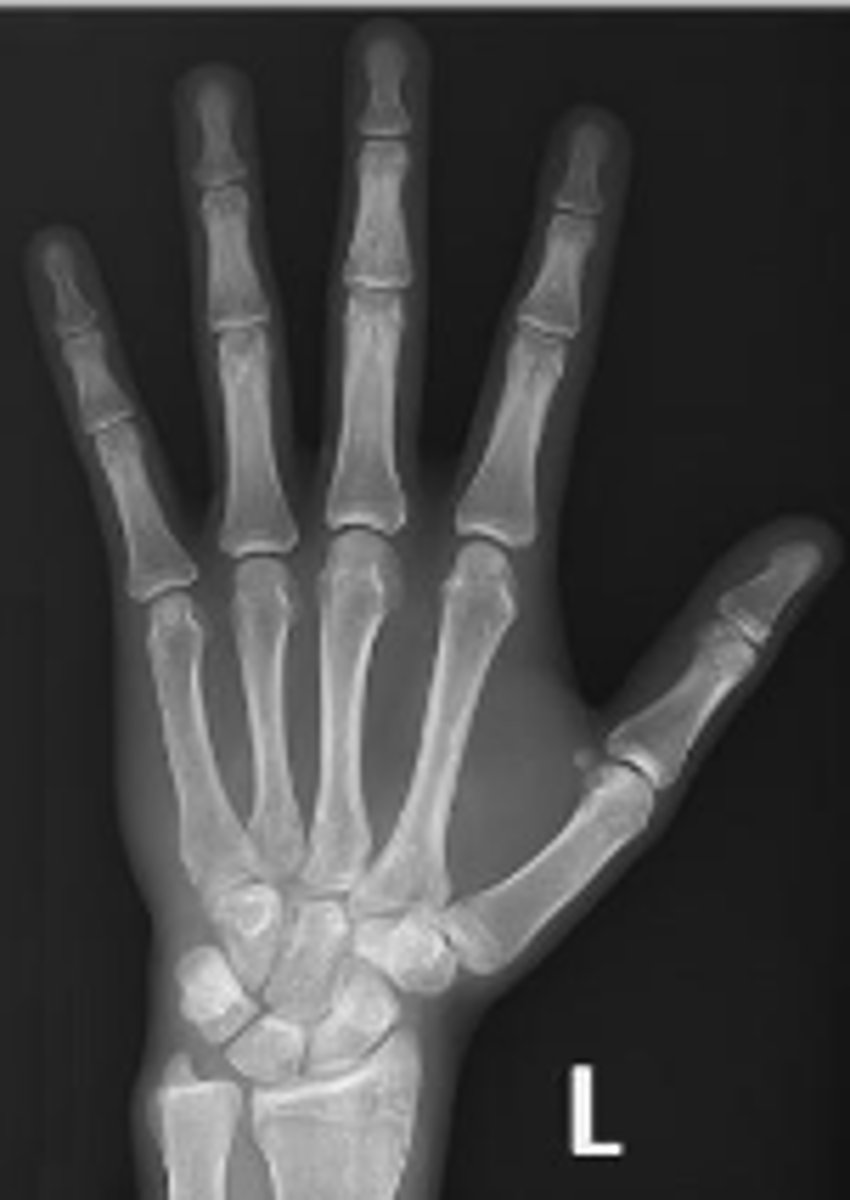

PA of the left hand

What is the name of the radiographic view?